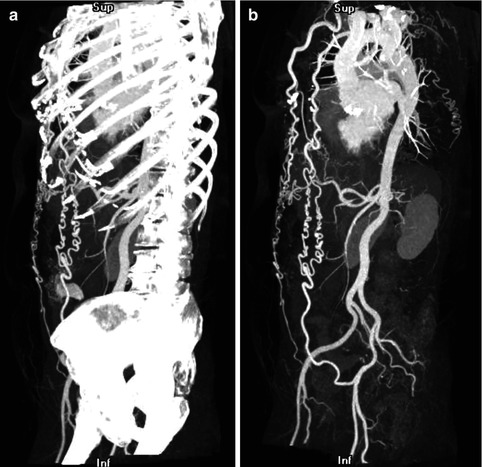

Fig. 5.6

(a) Maximum intensity projection (MIP) technique applied to the entire image volume in a patient with aortic coarctation. The bones obscure the vascular structures. (b) Thin-slab MIP in the same patient: The high-attenuation voxels of the bones are removed, leading to an improved visualization of the vascular structures and the collateral circulation in aortic coarctation